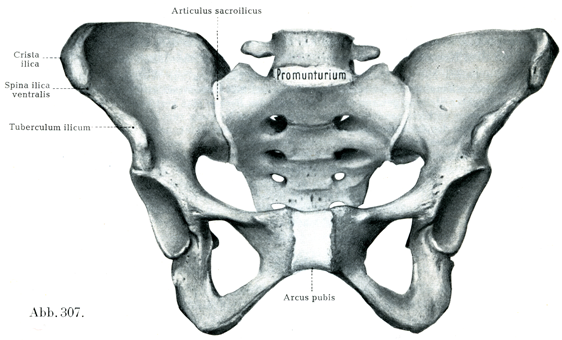

[図306, 307]女の骨盤(9/20),図306は前上方から,図307は前方からみる.図306では分界線が白い境界線であらわしてある.

(H. Virchowの標本による.椎間円板・恥骨結合・仙腸関節は自然の厚さを保っておぎなわれている.)